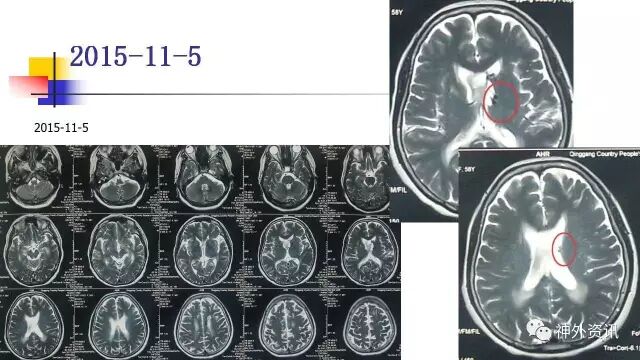

手术过程